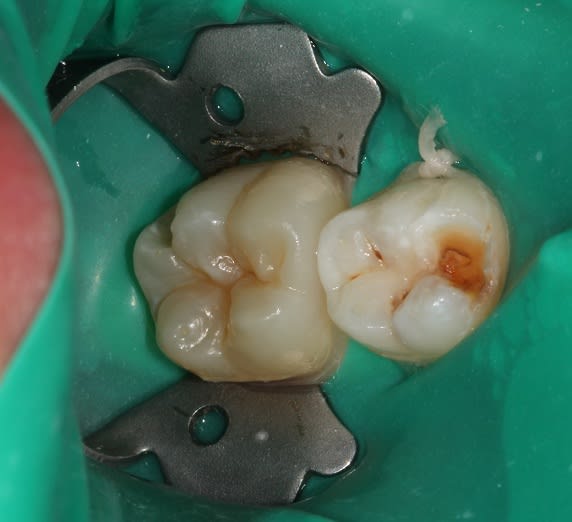

P1020069_njipcn.jpg

Voir le message contenant cette image